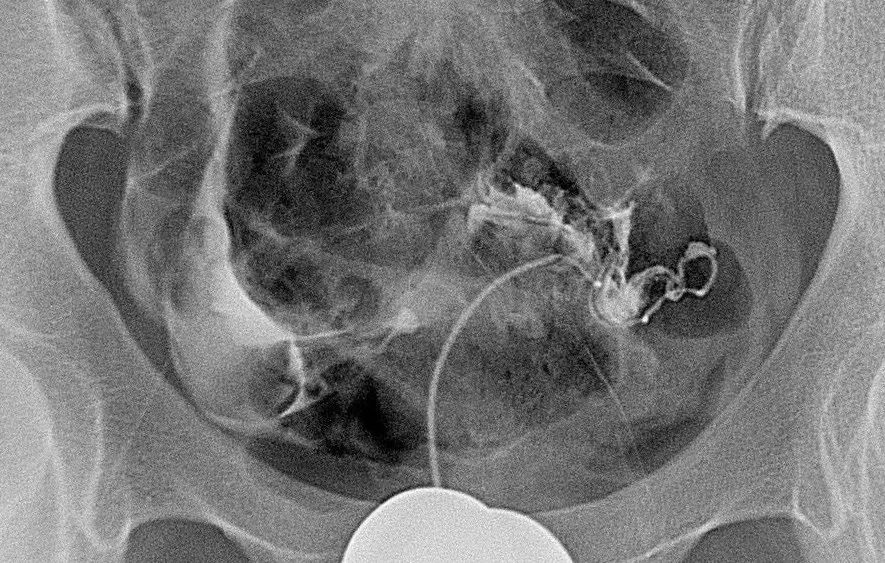

因此,并不是所有的介入治疗都需要多次进行的。比如:像动脉瘤、主动脉夹层、部分血管瘤、子宫肌瘤、囊肿等的介入治疗,很可能一次就能够解决问题,部分没有扩散转移的恶性肿瘤也有可能通过一两次的介入消融治疗得到根治。

输卵管性不孕症,很可能一次介入再通即可达成“做妈妈”的目标